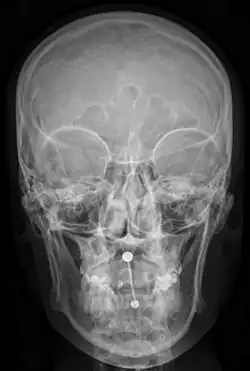

Piercings und bildgebende Verfahren

Im medizinischen Bereich kommen zunehmend bildgebende Verfahren, wie Magnetresonanztomographie oder Computertomographie zum Einsatz, welche mittels gezielter Röntgenstrahlung oder starker Magnetfelder einen Blick ins Innere des Körpers ermöglichen. Hierbei können Piercings unter Umständen ein Problem darstellen. Dies gilt jedoch nur für Piercingschmuck aus ferromagnetischem Metall, andere Materialien (Acryl, PTFE, Titan, organische Stoffe) stellen keine Einschränkungen dar.

Bei mit Röntgenstrahlen operierenden Geräten wie einem Computertomographie-Scanner kann ein Piercing unter Umständen eine darunterliegende Stelle verdecken und für die Bildgebung unsichtbar machen (beispielsweise kann ein Brustwarzenpiercing in einer radiologischen Untersuchung einen in unmittelbarer Nähe liegenden Tumorknoten verdecken und unerkannt lassen).

Im Fall von mit Magnetfeldern arbeitenden Geräten (Magnetresonanztomographie) besteht einerseits die Möglichkeit, dass der Schmuck sich stark erhitzt, zum anderen wird eine hohe Zugkraft auf den Schmuck ausgeübt, was im schlimmsten Fall zum Ausreißen führen kann. Um Schmerzen und Verletzungen zu vermeiden, sollte der Schmuck vorher entfernt werden (sofern dieser ferromagnetisches Metall enthält).